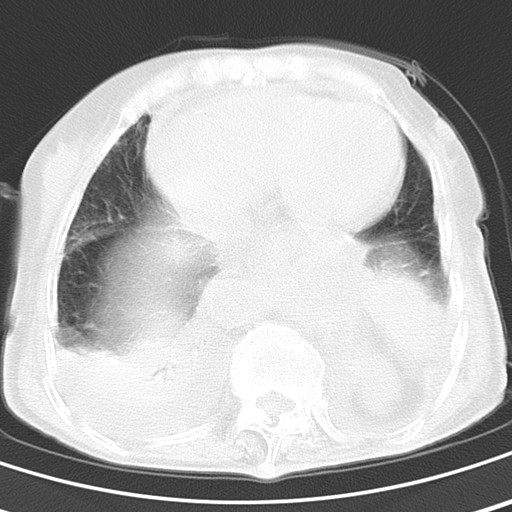

女,93岁,摔伤后检查。

右肺炎症,心功能不全伴双侧胸腔积液,右下肺膨胀不全,食管裂孔疝,冠脉钙化,心包少量积液,左侧肋骨骨折,请上传骨窗.

食管裂孔疝

创伤性湿肺,双侧胸腔积液。可能有食管裂孔疝,进一步检查。骨折有无根据自己的机器及片子再仔细看吧。

右侧锁骨\\肩胛骨骨折、右侧湿肺,心功能不全伴双侧胸腔积液,右下肺膨胀不全,左膈破裂或食管裂孔疝,冠脉钙化,心包少量积液,请上传骨窗.

右肺炎症,心功能不全伴双侧胸腔积液,右下肺膨胀不全,食管裂孔疝,冠脉钙化,心包少量积液,左侧肋骨骨折,右肩甲骨粉碎性骨折。93岁,高寿哇!

右肺炎症,心功能不全伴双侧胸腔积液,右下肺膨胀不全,食管裂孔疝,冠脉钙化,心包少量积液,左侧肋骨骨折,右肩甲骨粉碎性骨折。